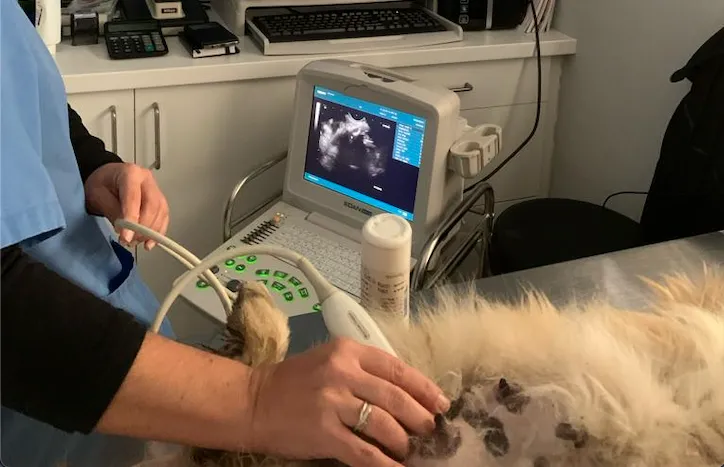

Ecografía para una Evaluación Detallada

La ecografía es un método no invasivo que utiliza ondas sonoras para crear imágenes de los órganos internos. Es especialmente útil para examinar el abdomen y el corazón, proporcionando información valiosa sobre la estructura y función de estos órganos